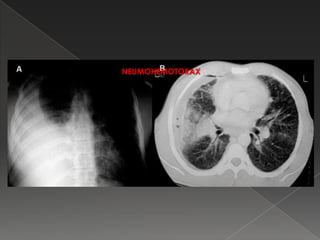

NEUMOHEMOTORAX